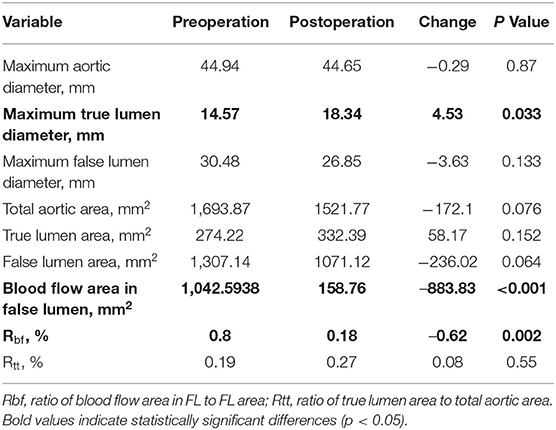

After RBS, 9 patients experienced abdominal segmental complete thrombosis. Comparison of the preoperative and the latest postoperative data showed significant differences in three indicators of aortic remodeling at the max diameter level of the total aorta. The maximum TL diameter was significantly increased (14.57 to 18.34 mm, p ≤ 0.033), while decreases in blood flow area in the FL (1042.59–to 158.76 m2, p < 0.001) and Rbf (ratio of blood flow area in FL to FL area) (80–18%, p = 0.002) (Table 3), were observed. In terms of outcomes of involved visceral arteries, all patients exhibited patent visceral arteries. A total of 12 patients experienced good visceral artery blood perfusion, and 1 patient exhibited mild visceral artery stenosis related to congenital renal artery malformation.

Figure 5 shows the comparing results of all the changing ratios between the latest follow-up and preoperative data in two groups. The changing ratio between RBS and paired non-RBS patients in total lumen area (dif = −0.89, p = 0.007), FL area (dif = −1.07, p = 0.028), and blood flow area (dif = −0.90, p = 0.015) shows significant difference, which means patients receving RBS are more likely to decrise the areas of total aortic lumen, true aortic lumen, and blood flow in the FL than those in non-RBS. As for the changing ratio of other items, although the results are not statistically significant, all the changing ratios in RBS group have the positive trend than those in non-RBS group.

Clinically, the aortic diameters and FLT status are important indicators for evaluating the aortic remodeling due to their close relationship with complications. The International Registry of Acute Aortic Dissections (IRAD) revealed that an aortic diameter of 5.5 cm was associated with a 4-fold increase in mortality (34, 35). Importantly, a FL diameter larger than 22 mm is predictive of an aneurysm with a sensitivity of 100% and specificity of 76%. Even though the true lumen diameter can change with blood pressure and cardiac cycle, it is still an important predictor of blood support to vital organs and tissues (36, 37). Moreover, complete FLT is the ultimate goal of treatment since it indicates a good prognosis (11). In the present study, RBS induced positive aortic remodeling both in self-control and matched pair comparison. In self-control results, RBS patients received significantly positive differences in maximum true lumen diameter, blood flow area in FL and Rbf, while receiving significant benefits in areas of total lumen, FL and blood flow in matched pare comparison. Also, complications in RBS are acceptable while those in non-RBS was more fetal and severe. Therefore, RBS has huge clinical application prospects and provides new insights to solve aortic dissection involving visceral arteries, especially zones 6–8 (38).